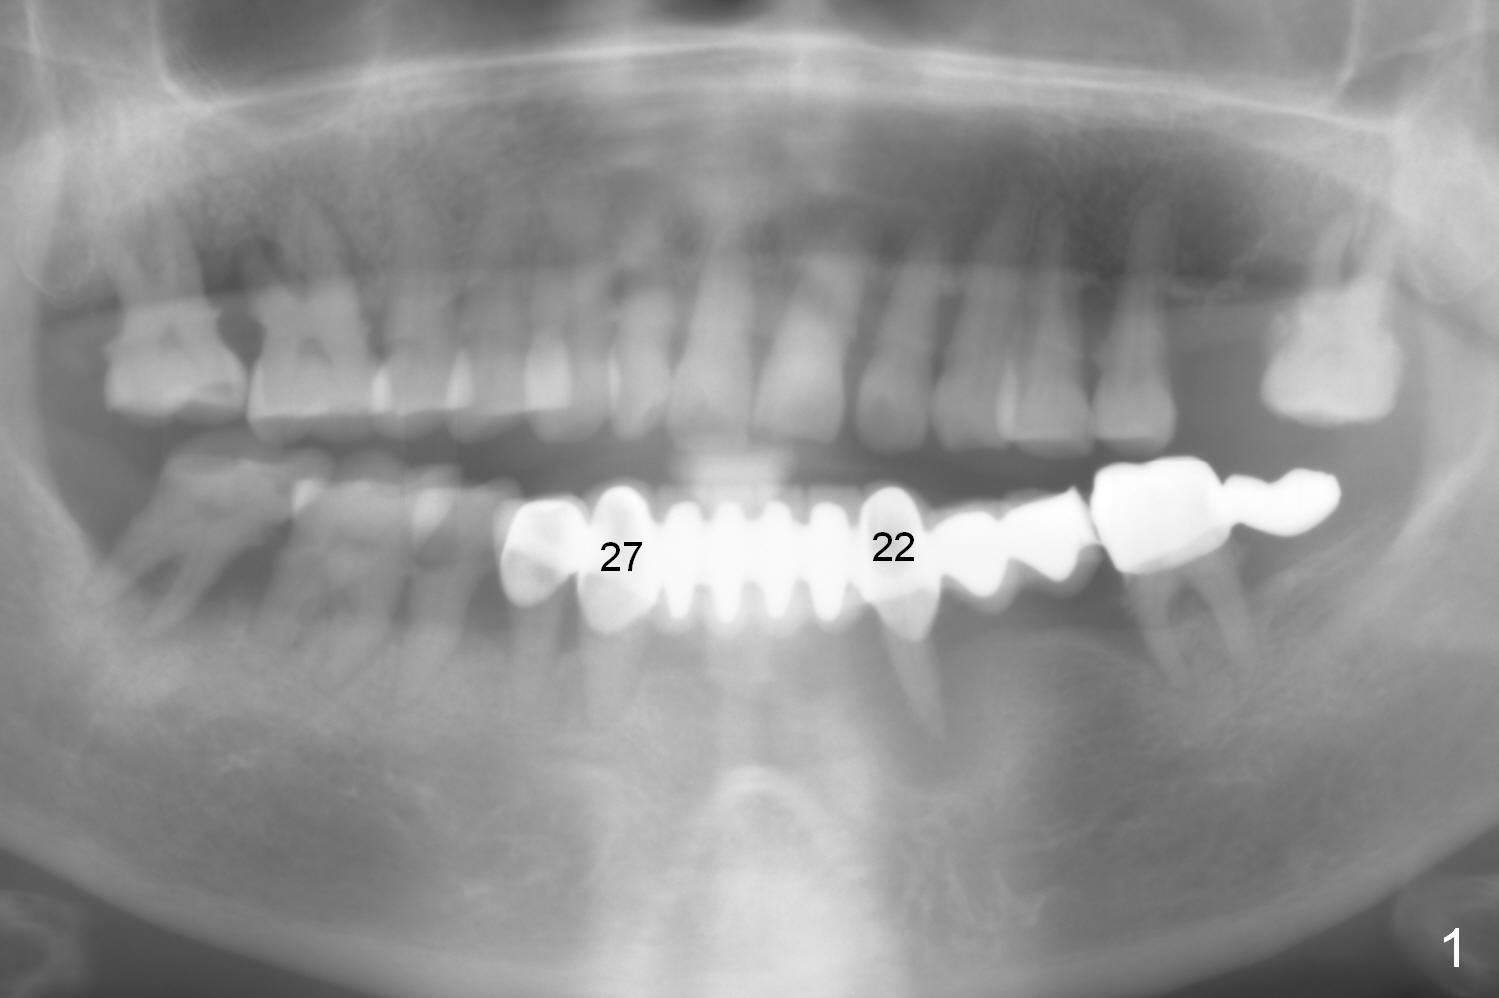

A 72-year-old woman has severe pain associated with one of three abutments of a long-spanned bridge (Fig.1,2: #22). The lingual calculus is extremely large (Fig.3 C). When the bridge is sectioned between #26 and 27, the tooth #22 is easily separated from the socket (Fig.4). In fact, the large supragingival calculus causes hemorrhagic indentation in the lingual vestibule (Fig.5,6: I). Due to finance, socket preservation is done at #22 with 6-month collagen membrane buccally and .5-1.5 mm allograft and collagen plug (Fig.6 *).